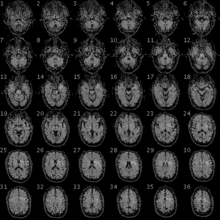

IRMf de la tête d'un participant au Personal Genome Project.